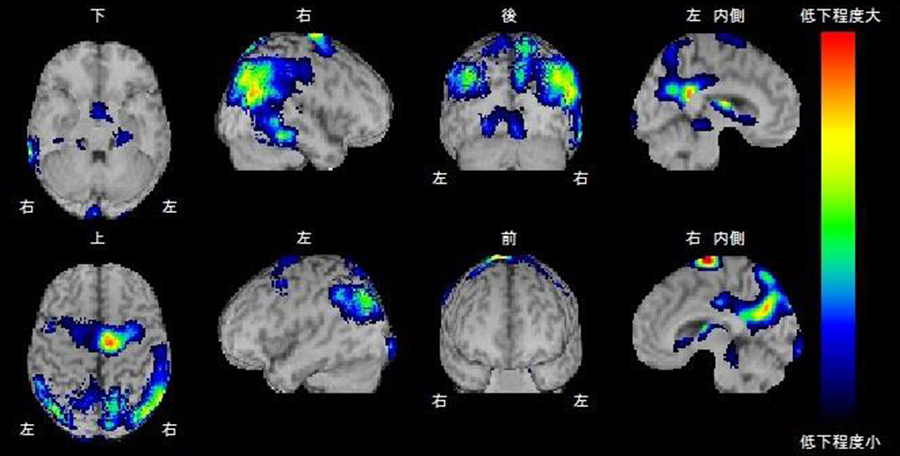

得られた脳血流画像を標準脳の形態に変換し統計学的な手法を用いて解析を行うソフトを使用することで、アルツハイマー型認知症やレビー小体型認知症など認知症の早期診断や病型診断に役立っています。(図2統計学的解析ソフト)

患者さんの検査結果